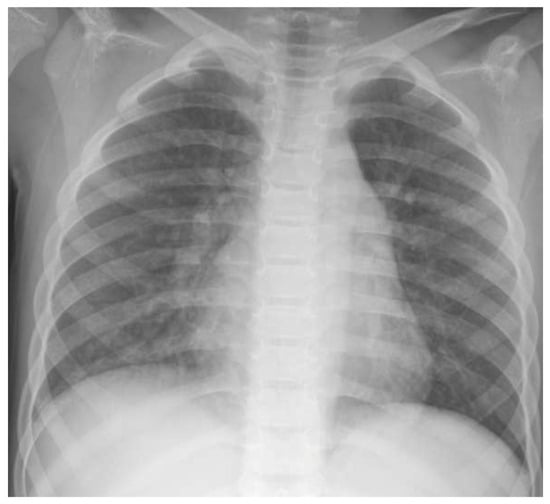

At admission in the ED, physical examination was remarkable for tachycardia (130 times/minute) and tachypnea (40 times/minute); peripheral oxygen saturation was 92% with slight intercostal retractions and wheezing on lungs auscultation. Blood tests showed increased leucocytes (25,000/mmc, N 16,530/mmc) and sodium level (147 mEq/L), with pH 7.32, pCO2 40 mmHg, and HCO3 20 mEq/L. A chest X-ray revealed a bilateral lung infiltration, with a consolidation area over the right lung (Figure 1). The patient received high-flow oxygen therapy for 24 h with a full recovery.

Figure 1. Chest X-ray showing bilateral lung infiltration, with a consolidation area over the right lung.